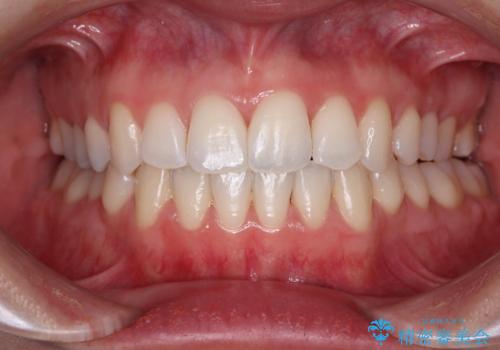

非抜歯、ワイヤーでの矯正治療。歯のがたつき、顎のズレ、出っ歯を治す。インビザラインが使えない方